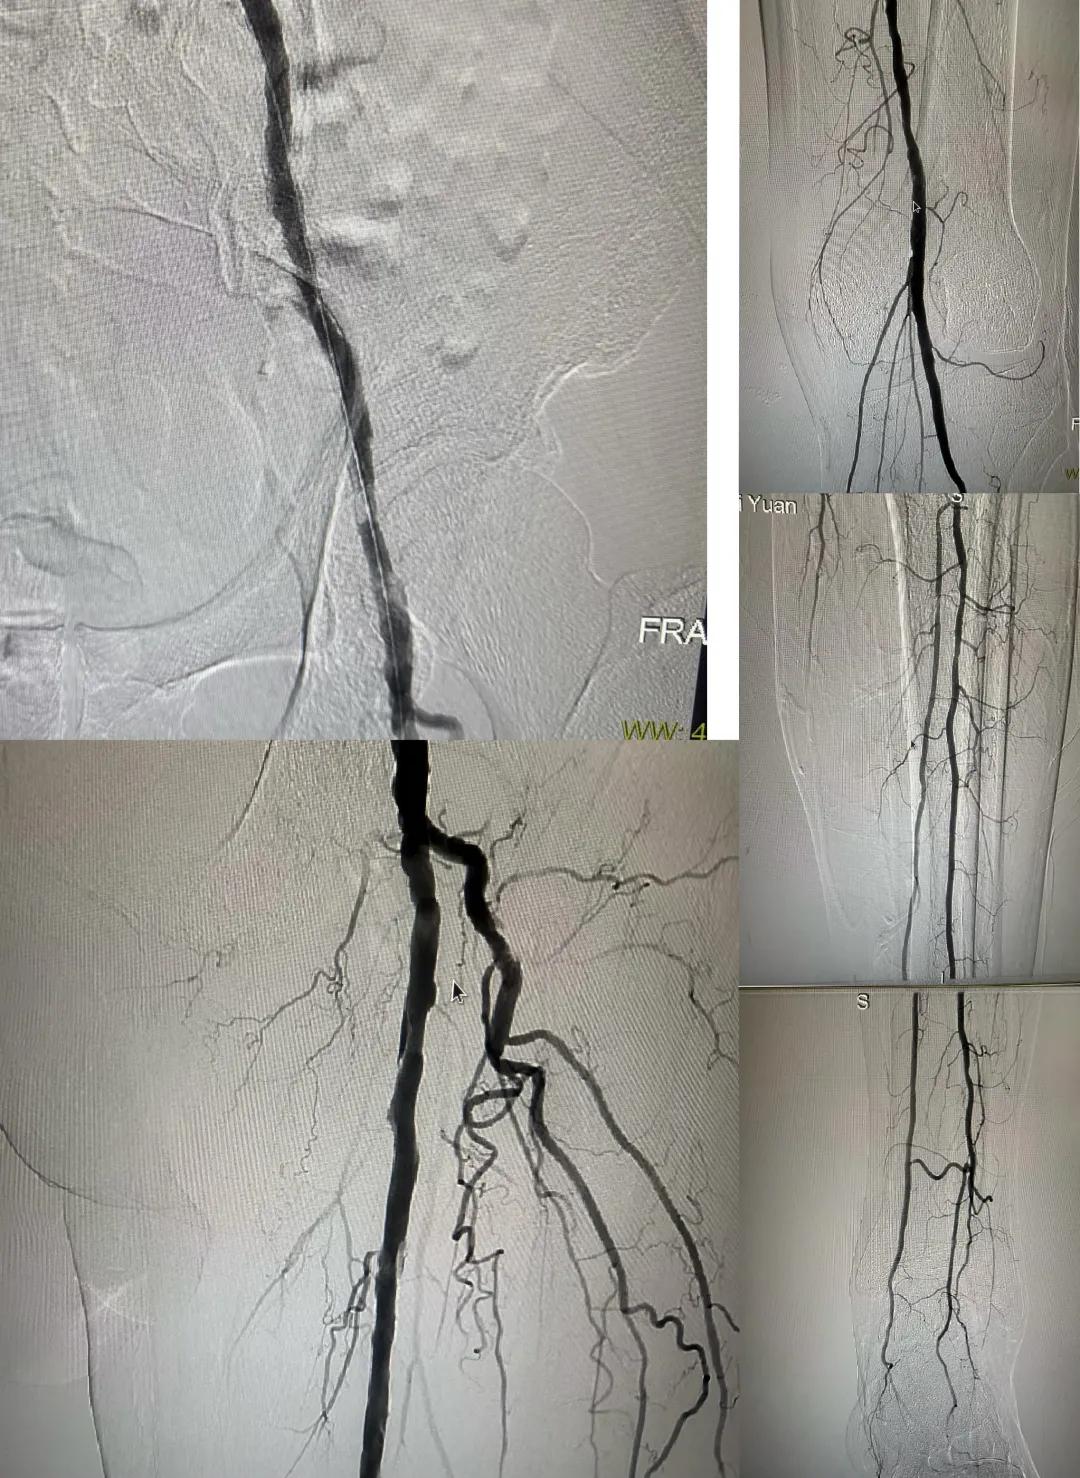

患者,男,73歲,約15天前出現(xiàn)左側(cè)腳面腫痛,間歇性跛行,左足第三足趾壞疽,遂來市中醫(yī)院就診,以“下肢動脈硬化閉塞、糖尿病足壞疽、”收住外二科,評估患者病情后需實施左下肢球囊擴(kuò)張成形術(shù)。術(shù)中造影見患者左側(cè)髂動脈、股淺動脈階段性重度狹窄。經(jīng)外周球囊擴(kuò)張術(shù)后,再次造影見股淺動脈、髂動脈血流通暢,膝下及足部血流速度較前改善。

術(shù)后已疏通血管成像